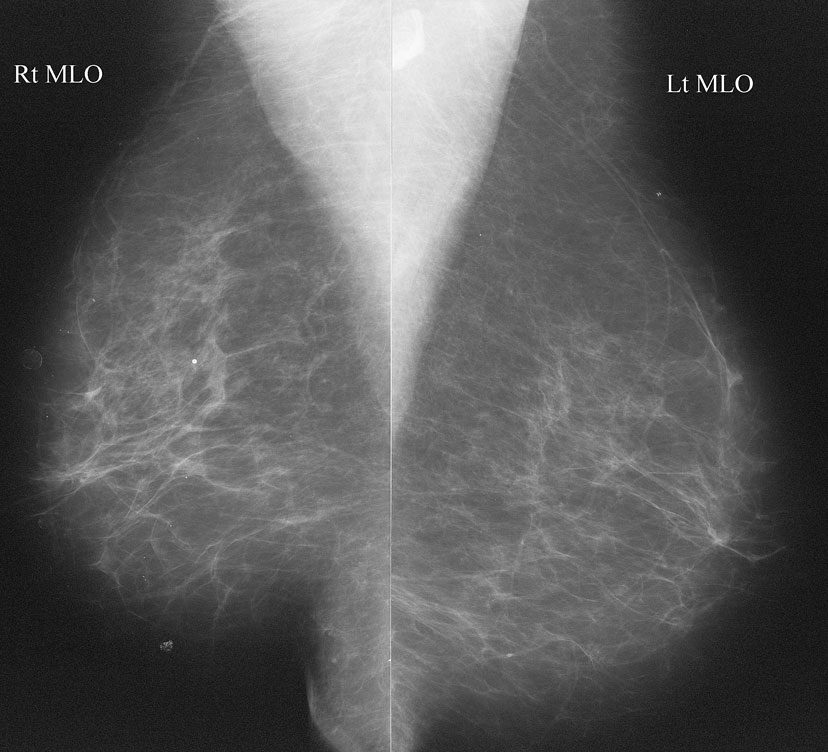

Что такое маммография: важность, процесс и результаты

Раздел: Необычные решения